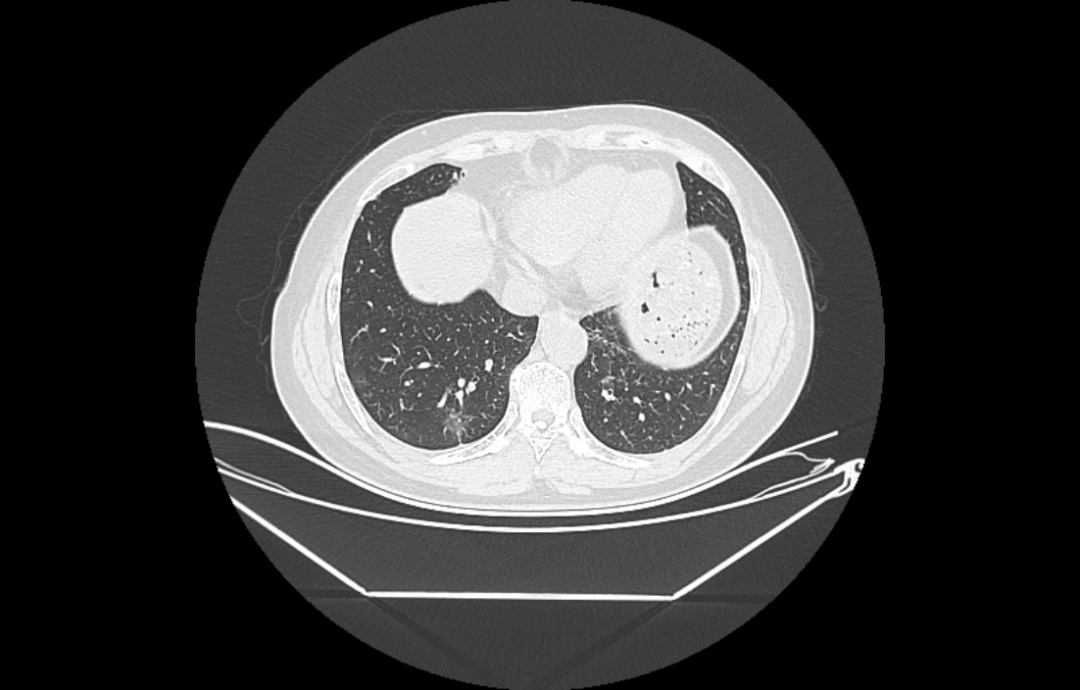

接诊的胸外科主任黄永高认真查看了老李的影像资料:病灶在右下肺后外基底段(S9+S10),直径约2cm,毛玻璃成分为主。考虑到老李的情况,黄主任决定采取右下肺后外基底段切除术,以最大限度地保留患者的肺功能,避免进行整个肺叶的切除。但由于S9+S10段的解剖结构复杂,变异较多,为了确保手术的精准与安全,黄主任决定利用先进的肺小结节AI(人工智能)三维重建技术进行术前规划。

(术前模拟,术前手术规划)

在AI技术的辅助下,胸外科手术团队得以清晰地看到病灶的三维结构,以及周围血管、神经的精确分布。这不仅大大提高了手术的精确度,还使得手术过程更加顺畅,减少了不必要的创伤。

遇到复杂肺段切除病例术前进行AI三维重建,AI三维重建能够精准重建了患者的肺部模型、肺结节三维详细分布图,制定术前规划及手术方案。通过三维重建技术建立肺部模型,明确肺结节的详细位置及与周围动脉静脉、支气管之间的关系,精准规划了手术路径及切除范围,就像开车安装了GPS导航一样,使手术思路特别清晰,能够最大限度地保留患者肺功能,提高手术的安全性、精确性,缩短手术时间,再加上单孔胸腔镜技术,真正实现了胸外技术的“微中再微”。